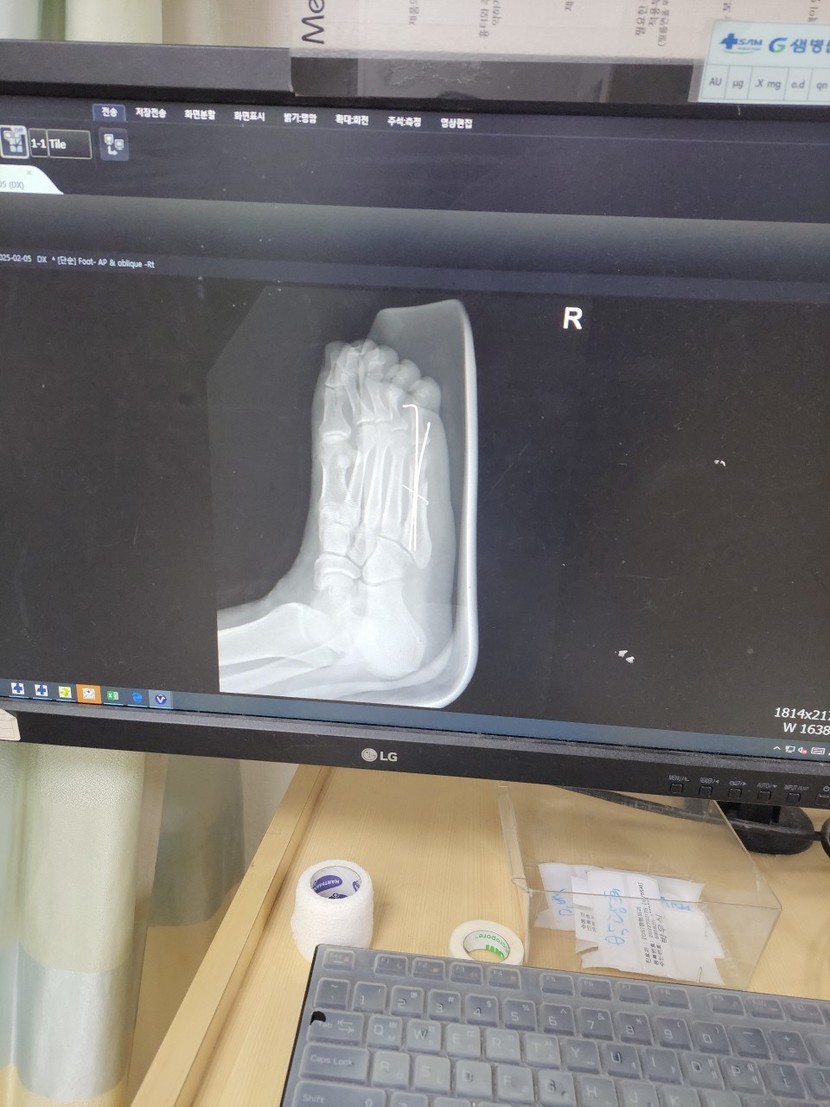

25.02.10 118 읽음 현재 상태 convertkch 구독하기 12 16 콘텐츠의 수익 3 뼈가 붙는게 6~8주라니최소 2월말까지는지금처럼 재택근무하며 버텨야 할듯일주일에 한번내지 두번 통원치료 빼고는집에만 있어야하니 무지 답답하네요.다들 행복한 하루 보내세요 16 0 / 300 입력